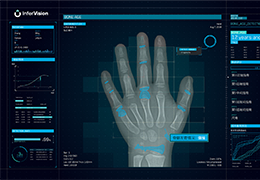

View X-Ray CT & MRI Scans Fast and Easily

Designed for surgeons, Pro Surgical 3D makes it easy to view patient scans quickly. Pro Surgical 3D facilitates the optimal 3D treatment and assessment workflows based on X-ray CT and MRI scans – and best of all, it’s FREE!

High-quality and fast 3D reconstruction and 3D rendering

Performs 3D reconstruction and volume rendering.